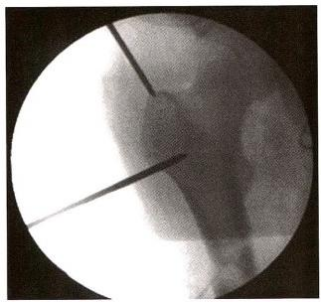

撬拔技术:先用4mm 克氏针经皮插入,纠正近端前屈、外展、外旋, 然后开口定位(图12-3)。

图12-3 复位与开口